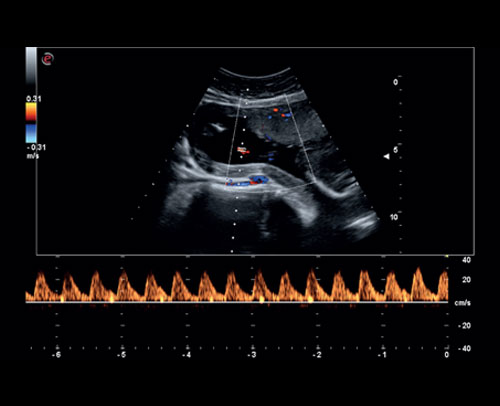

PW Doppler - pupeční šňůra

Vyšetření střední mozkové tepny s PW Dopplerovým módem.